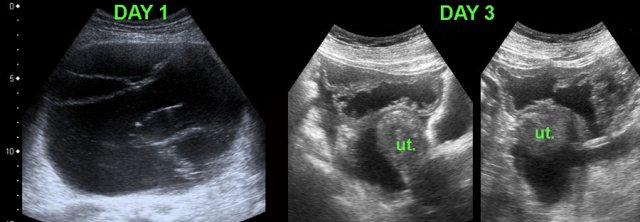

TOA case 3

Large

left sided TOA with air-configurations.

This is a rare finding in TOA, successful

treatment with only antibiotics.

TOA case 4 (infected endometriotic cysts)

These images are of a 29-year old woman, suspected for appendicitis. CRP 185, WBC 17.

US shows a normal compressible appendix, thereby excluding appendicitis.

Large, thick-walled, septated cystic structures, filled with debris-like material, were found on both sides of the uterus (ut.), touching each other posteriorly (“kissing ovaries”).

This is somewhat suspect for bilateral infected endometrotic cysts.

The patient was treated with antibiotics and laparoscopic drainage.

There was a protracted course, but eventually regression of the abnormalities.

An MRI six months later, demonstrated all the signs of deep infiltrating endometriosis, also invading the rectum, thereby confirming the diagnosis of endometriosis.